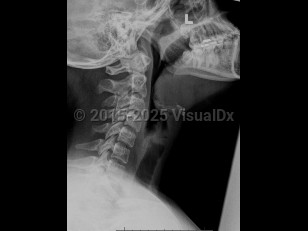

Sore throat, Cervical lymphadenopathy, 50-59 year old Female

EpiglottitisEpiglottitis

Retropharyngeal abscess